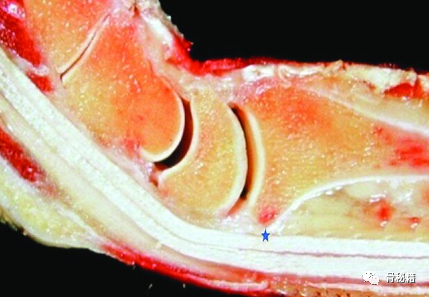

由于桡骨远端存在掌倾角,桡骨远端掌侧存在一个分水岭。背侧剪切损伤表现为背侧边缘骨折,并且通常与腕骨的背侧不稳定相关。这些损伤通常有凹陷的关节碎片,并可能有额外的桡柱受累。掌侧剪切损伤表现为掌侧边缘移位骨折并导致腕骨掌侧不稳定。这种模式通常具有多个关节碎片并且高度不稳定。桡骨剪切性骨折(驾驶员骨折)通过穿过桡骨茎突,延伸到桡腕关节的特征性横向骨折线来识别。这三类,都属于极远端骨折

AO的教科书建议把钢板放置在分水岭以近端来固定骨折减少屈肌腱损伤分水岭线定义为一条标记掌侧边缘最掌侧的理论线大多数医源性肌腱并发症包括屈肌腱:拇长屈肌 (FPL) 肌腱断裂和屈肌腱腱鞘炎

但是这样的边缘骨折 靠传统的钢板很难固定,容易引发骨折移位,由于这里有掌侧韧带和相应的关节囊附着。